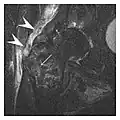

-

a -

b

Figure 13: Partial osseous avulsion of the gluteal muscles at the greater trochanter in a 59-year-old man who presented with the right hip pain without a history of trauma. Lauenstein view and anteroposterior and radiographs (not shown) did not show an obvious fracture line or disruption of bony contours in the acetabulum or the right femoral neck. (a) Coronal T1-weighted MRI displays an incomplete fracture line extending partially from the greater trochanter (arrow). (b) Coronal short tau inversion recovery MRI shows heterogeneous hyperintensity in the same region (arrow) as well as hyperintensity within the gluteus medius and minimus muscles (arrowheads) consistent with tissue edema and hematoma.[1]